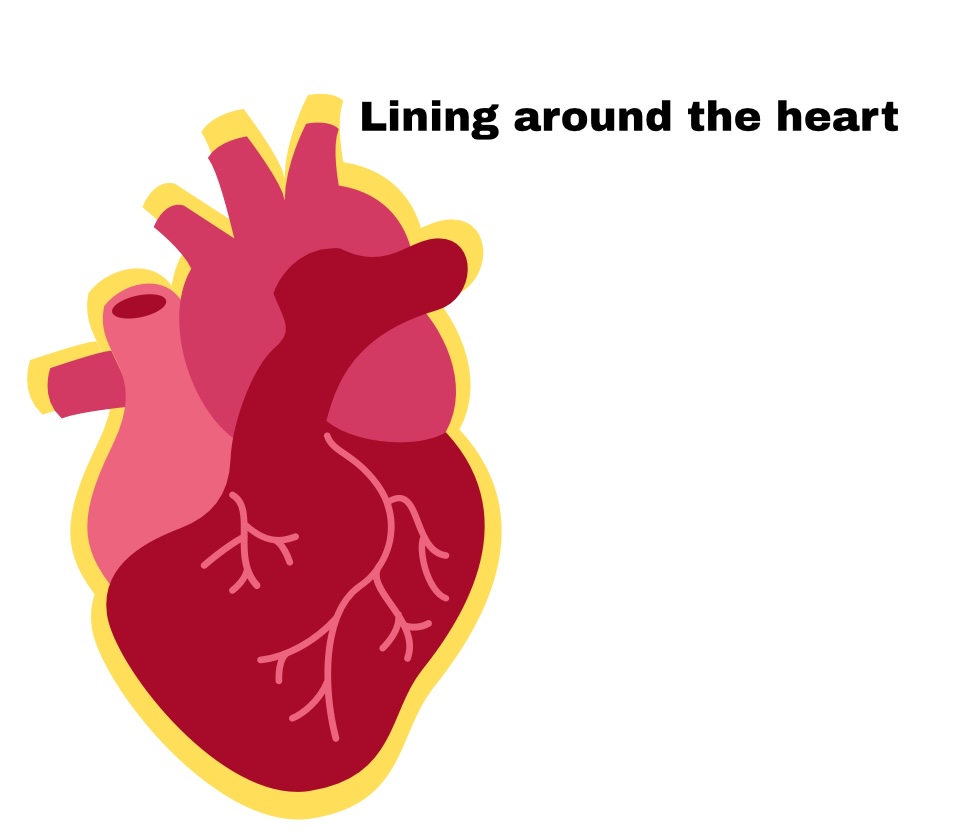

The heart=

Pericardium

Pericardium

Sac around heart

Partial Pericardium

Outer layer

Visceral Pericardium

Deep layer (surface of organ)